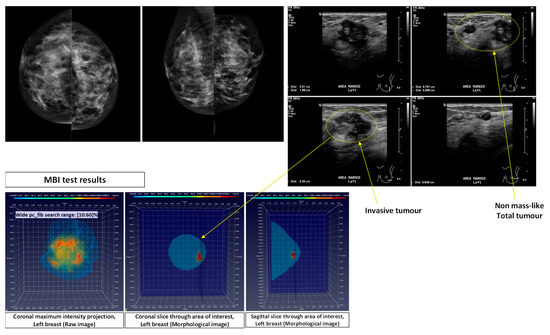

- Patient 032: Group-1: 54-years old patient with an Invasive Lobular Carcinoma (ILC) of size 30 mm (MRI data) at the 12 o’clock position of the Right Breast. Breast density: BIRADS Category c, Volumetric Breast Density (VBD) = 13.3%.

- pc_fib parameter setting in multiple search ranges: A large variability exists in the dielectric properties of each breast tissue type over the population, as demonstrated by multiple studies involving ex-vivo dielectric measurements of a large sample of excised breast tissues [18,19,20,21]. Considering that the full dielectric map of each breast cannot become practically available, data-driven techniques are employed in the Wavelia QIF to deduce the unknown dielectric properties of the healthy breast tissue in each breast, by assessing the pc_fib parameter. The pc_fib parameter, which is involved in the formulation of the illumination vector of the MBI sensor array, is physically associated with the percentage of fibro-glandular tissue along the propagation path within the breast, from a given transmitting antenna to the interrogated imaging pixel and back to a given receiving antenna, as defined in Equations (1)–(3). The Wavelia QIF generates a set of parametric MBI radar images under various assumptions on pc_fib. The generated set of parametric images is further evaluated in terms of focusing, using the image curvature [22,23] as a focusing quality measure. To better handle the heterogeneity of the breast and potentially better reveal the non-uniform angular response of the breast lesions to MBI, the pc_fib parameter setting is performed independently in each azimuthal imaging sector, while employing multiple search ranges. In the Wavelia QIF, X1 wide and X2 narrow pc_fib parameter search ranges are systematically employed for image formation, thus a total number of X = (X1 + X2) MBI images are formed per patient’s breast.

- Wide pc_fib search range #1 (W1): pc_fib ϵ [10 20 30 40 50 60]%

- substantially increased busyness value was associated with more heterogeneous lesion patterns, which may be interpretable as being indicative of distributed non-mass like ILC’s, such as in the Patient 032 case.